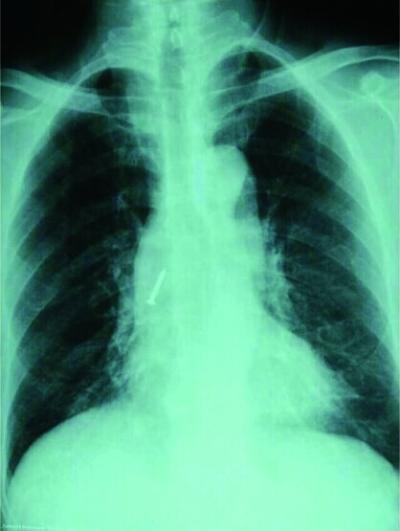

据介绍,10月26日下午,白先生的家人带着他赶到医院看急诊。医生给白先生做了CT后,发现有一颗钉子卡在了他右肺的中间段支气管里,钉子大头朝下,尖端直指纵膈。

在把白先生送到朝阳医院之后,医生为他进行了手术,在手术过程中遇到了一点困难。“从鼻腔导入气管的冷冻探头将钉子往外拉,拉到主气管时,钉子尖端反复扎到气道壁,如果再继续操作会出现气管损伤。这时换用了异物钳,钳住钉子的尖端往外拉。”医生说,近三厘米长的水泥射钉成功地取了出来,整个过程仅用了十分钟左右的时间。